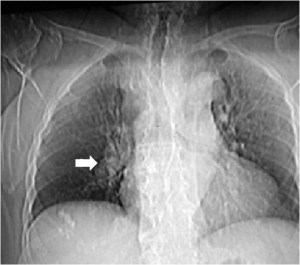

SIGNO DE LA CISURA INCOMPLETA, DE LA PSEUDOCAVIDAD O SIGNO DE LA ESPINA DE ROSA

Es un signo de derrame pleural en la cisura mayor visible en la radiografía de tórax, en un paciente con cisura mayor incompleta. Es más frecuente verlo en el lado derecho ya que en el izquierdo la silueta cardiaca puede ocultarlo.

La presencia de una zona radiotransparente perihiliar, circunscrita lateralmente por una línea curva bien marcada (flecha blanca), en cuya periferia se observan varios grados de opacidad, corresponde a la presencia de líquido en la cisura mayor incompleta. La línea curva termina en un extremo en punta (flecha roja), que estará más cercana al hilio cuanto más completa sea la cisura.

El nombre de pseudocavidad hace referencia a la radiolucencia perihiliar, mientras que el de espina de la rosa se refiere a la morfología de la opacidad, con el extremo en punta.